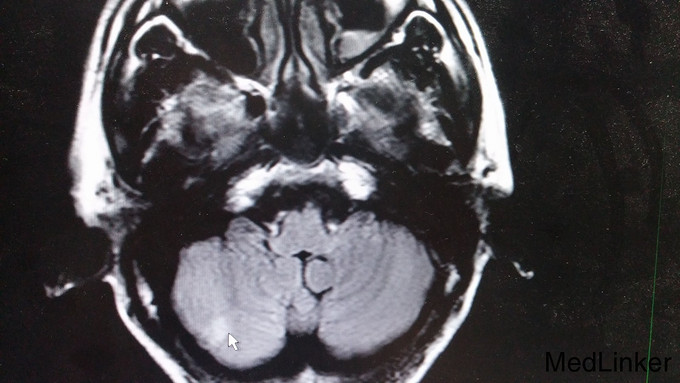

双侧向内侧凝视,左眼外展不能。辅查: 1. 血管炎指标五项、抗核抗体谱、抗心磷脂抗体未见明显异常,血沉27mm/h。 2. 头颅MRI:双侧放射冠区、左侧基底节区及右侧小脑半球多发梗塞灶(右侧小脑半球亚急性期脑梗塞)。

头晕、头痛好转,左眼外展受限同前。讨论: 1.患者左侧外展 受限,定位于左侧脑干,MRI示右侧桥脑腔隙性梗死,非责任病灶; 2.一般梗塞不会引起头痛,住院前10天有腮腺炎病史,尽管血管炎指标阴性,仍考虑血管炎而非脑梗的可能性大。